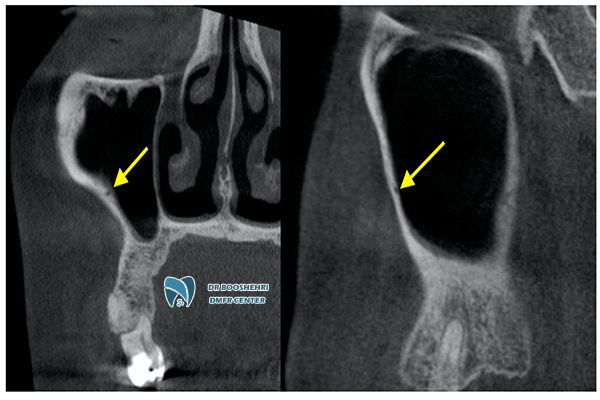

A major advantage of Jaw and Gum Radiology is its ability to provide high-quality, three-dimensional images of the mouth and jaw structures. These images are particularly useful for diagnosing Gum Disease in Special Patients. Patients with limited mobility often require specialized care, and traditional diagnostic methods may fall short in meeting their needs. By utilizing Jaw and Gum Radiology, healthcare providers can achieve more accurate diagnoses and develop effective treatment plans tailored to the unique needs of these patients.

Dental imaging for patients with limited mobility requires the use of advanced tools and technologies due to their unique needs. Methods such as CBCT (Cone Beam Computed Tomography) and panoramic imaging are utilized in Dental Imaging for Patients with Limited Mobility to provide comprehensive insights into the condition of their oral and gum health. These technologies not only ensure high accuracy but also reduce imaging time and enhance patient comfort.

These techniques not only help in identifying hidden issues but also in preventing more severe complications. For instance, Jaw and Gum Radiology can aid in the early detection of bone resorption, helping to halt its progression. Moreover, these technologies reduce the need for invasive examinations, offering greater comfort for patients.